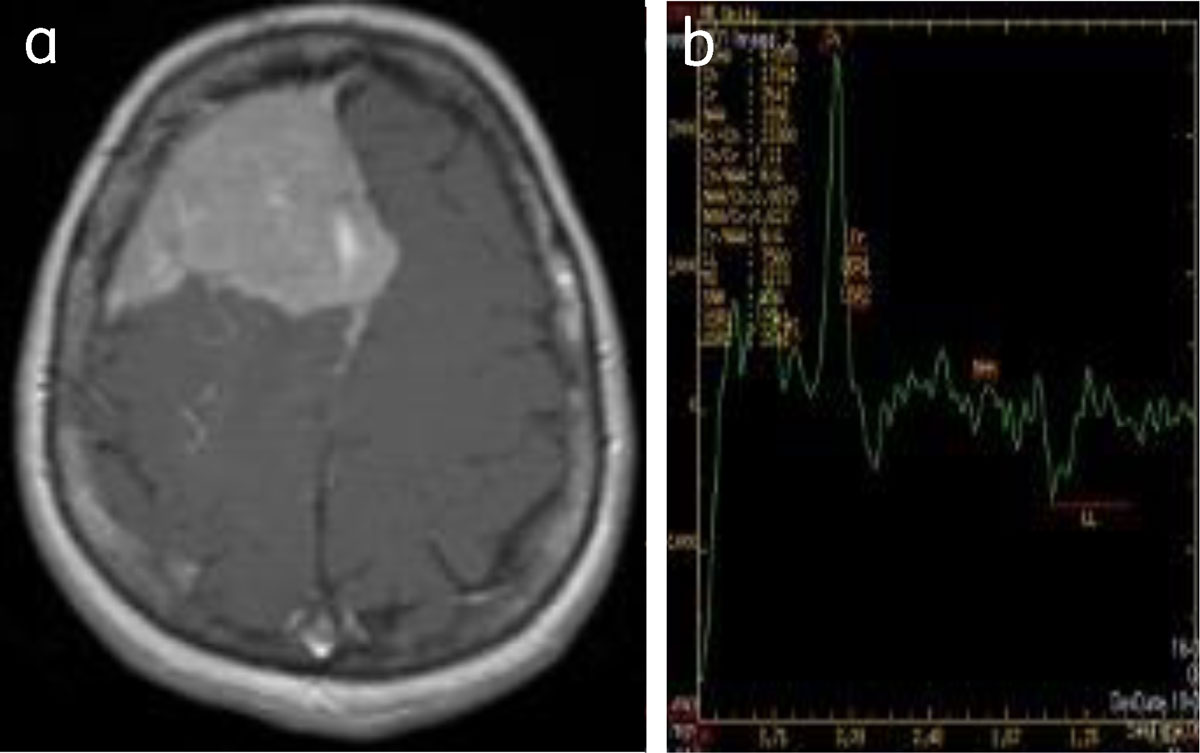

Figure 13

Convexity meningioma: (a) enhancing right frontal meningioma, (b) MRS shows choline peak with reduced NAA.